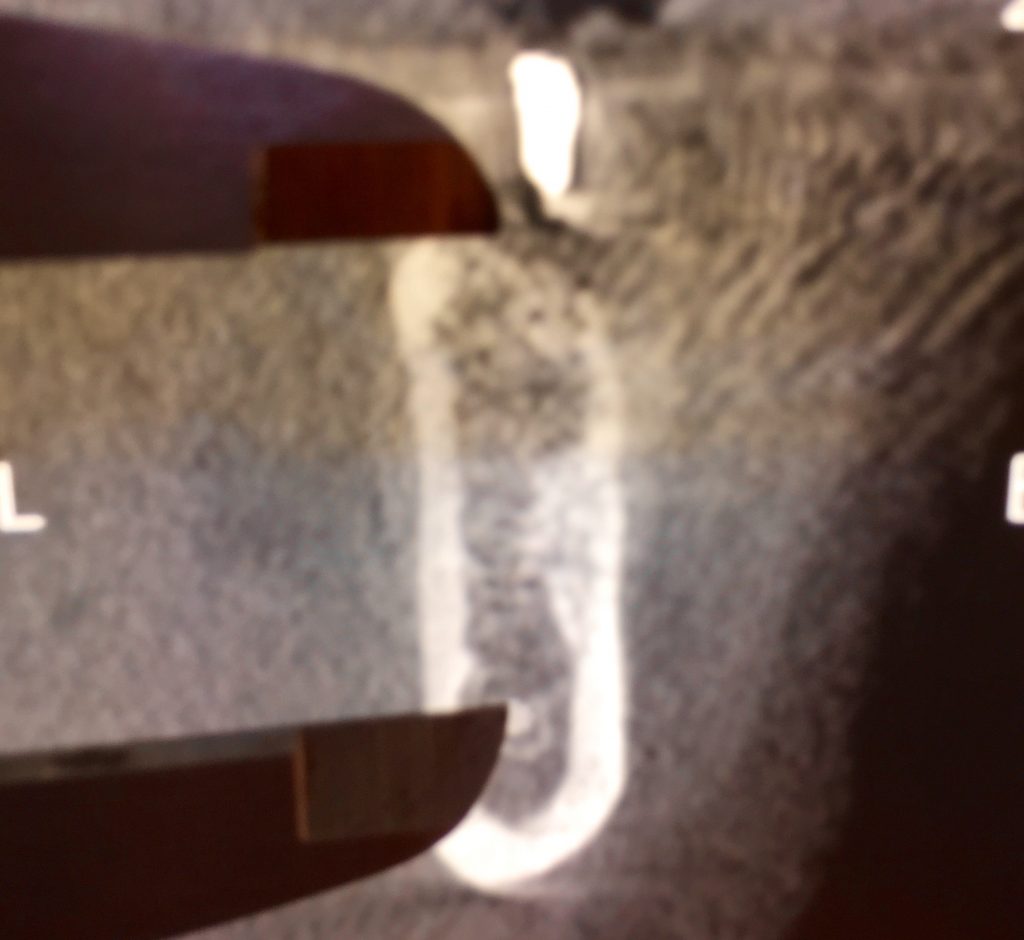

FIG: 14-15-16-17-18-19-20

Fig. 14

Fig. 15

Fig. 16

Fig. 17

Fig. 18

Fig. 19

Fig. 20